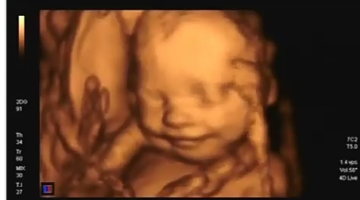

الحمل والولادة

حجم الجنين في الشهر الخامس بالفواكه

معرفة نوع الجنين من فخذ الطفل السابق بالصور

حرارة القدمين للحامل ونوع الجنين

هل يؤثر القولون على حركة الجنين

فقدان الشهية للحامل ونوع الجنين

أكل الثلج للحامل ونوع الجنين

ألم الجنب الأيمن للحامل ونوع الجنين

أكل البصل للحامل ونوع الجنين

البشرة الدهنية للحامل ونوع الجنين

البطن النازل للحامل ونوع الجنين

نسبة ph في البول للحامل ونوع الجنين